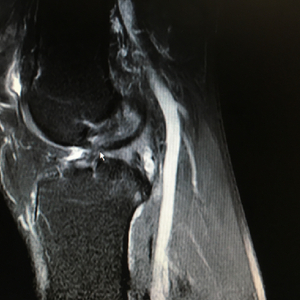

核磁共振检查发现,他的前叉韧带已经吸收消失,半月板也发生了退变磨损。上周,南医三院关节外科运动医学科副主任曾春为其重建了韧带,修整半月板等,目前恢复良好。不过,要想激烈运动,可就要等到两年后了。

南医三院院长蔡道章在为他查体的时候,一拉他的左腿,就说“应该是前叉断了”。核磁共振拍片确认前叉韧带断裂后,赵先生很懊悔,“觉得对自己很不负责任。”